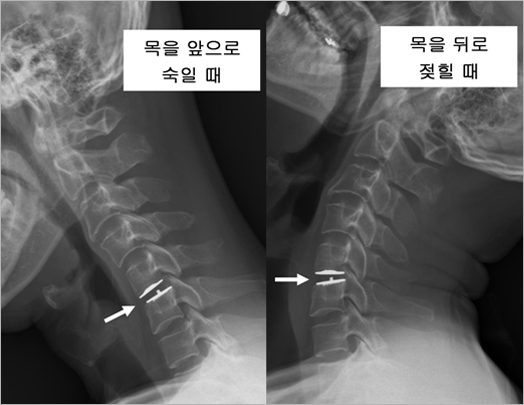

| 앞에서도 언급한 바와 같이 인공디스크는 기존에 행해지던 유합술의 단점을 보완하기 위해 개발된 것입니다. 그렇다면 유합술의 문제점이 곧 인공디스크의 장점이자 사용 근거가 될 것입니다. 다음에 열거하게 될 유합술의 대표적인 문제점은 척추외과 의사들 사이에서도 아직까지 논란의 여지가 많은 민감한 내용입니다. 따라서 여러분들께서 읽으시다가 혹시 혼란스럽거나 이해하기 어려울 지도 모르겠으나, 가급적 객관적으로 찬반 양론을 모두 다루도록 하겠습니다. 첫 번째, 유합술의 문제로 논란이 되고 있는 것 중 하나는 수술 부위의 인접 분절(바로 위 아래 추간판), 특히 위 분절에서 추간판의 퇴행성 변화가 발생할 가능성이 높다는 것입니다. 앞서 말한대로 목의 운동시 말랑말랑한 추간판, 특히 3번부터 7번 경추 사이에 있는 추간판들이 각자 변형되면서 움직임을 가능하게 만드는데, 쉽게 표현해서 이 중 하나가 유합술에 의해 고정되어 버리면 결국 이 일을 나머지가 나누어서 해야하고 따라서 남아있는 추간판에 과도한 부담이 가게 된다는 것입니다. 실제 실험 연구 결과에서도 추간판 하나를 고정하면 그 위 아래 추간판의 압력이 증가한다고 밝혀진 바 있습니다. 이렇게 유합술 위 아래 분절에 발생하는 방사선 검사상 추간판의 퇴행성 변화를 인접 분절 변성(adjacent segment degeneration)이라 합니다. 관련 연구가 많이 있지만 대체적으로 유합술 후 5년 이상 경과했을 때 약 25%정도에서 발생한다고 알려져 있습니다. 하지만 방사선 검사에서 이상이 있다고 해서 이것이 반드시 "목디스크" 증상을 일으키고, 또 한 번의 수술을 받게 하는 것은 아닙니다. 인접 분절 변성 환자 중 일부만이 실제로 새로운 증상을 경험하게 되는데 이러한 경우를 따로 구별하기 위해 인접 분절 질환(adjacent segment disease)이라고 합니다. 역시 여러 연구 보고가 있으나 대체적으로 수술후 1년마다 3%씩 발생율이 증가한다고 합니다. 예를 들어 100명의 환자에게서 경추 추간판 유합술을 시행했다면 5년 후에는 이 중 대략 15명(5년 x 3%/년 = 15%)에서 인접 분절 질환으로 또 한번의 수술이 필요하다고 할 수 있습니다. 그렇다면 인접 분절 질환을 일으키는 원인은 유합술뿐일까요? 반드시 그렇다고는 할 수 없습니다. 인간의 추간판은(신체 어느 부위도 마찬가지이지만) 사춘기 이후 점차로 노화되어 갑니다. 이 중 한 두 마디는 다른 곳 보다 먼저 노화가 진행되고 변성되어 "목 디스크"로 발전할 수 있습니다. 만약 이 추간판을 수술하지 않고 방치한다면 인접 분절에는 변성(노화 즉 퇴행성 변화)이 전혀 생기지 않을까요? 상식적으로 대답해서 언제든지 생길 수 있습니다. 경추의 한 마디만 혼자서 노화되기는 어렵기 때문입니다. 다시 말해 "인접 분절 변성 혹은 질환"은 유합술을 시행한 추간판의 인접 분절에도, 또한 수술하지 않은 추간판의 인접 분절에도 모두 생길 수 있는 상황이며, 유합술의 장기적 합병증인지 아니면 추간판 노화의 자연 경과인지 확실히 구분하기 어렵습니다. 이렇게 되면 다음으로 중요한 것이 그 빈도(발생률)입니다. 만약에 유합술을 받은 환자에서 그렇지 않은 환자, 즉 인공디스크 삽입술을 받았거나 그대로 방치한 환자에 비해 월등히 많이 발생한다면 유합술이 인접 분절 질환의 위험 인자로서 규명될 수 있습니다. 역시 많은 연구 보고들이 있었지만 아직까지 갑론을박이 많습니다. 즉, 유합술을 받은 환자에서 월등히 높은 발생률을 보였다는 의사들도 있고, 전혀 차이가 없었다는 의사들도 있습니다. 경추 인공디스크가 개발된 지 아직 충분한 시간이 지나지 않았기 때문이기도 하지만, 차차 진실이 밝혀질 것입니다. 두 번째 유합술의 문제점은 해당 추간판이 사라짐으로 인해 그 마디의 움직임이 없어진다는 것입니다. 이것은 논란의 여지가 없습니다. 유합술 후에도 해당 추간판에 움직임이 있다면 이것은 뼈가 잘 붙지 않은 것이므로 실패한 수술이 되며 이로 인해 목의 통증을 비롯한 이차적 문제들이 발생할 수 있습니다(그림 8). |

| • 그림 8 케이지를 이용한 유합술 후 목의 운동시 엑스레이 사진으로 해당 추간판이 완전히 유합되어 움직임이 전혀 없는 것을 보여줍니다. |

![]() |

| 인공디스크 삽입 후에는 움직임이 비교적 잘 유지됩니다. 이 때문인지, 척추외과 의사들 사이에서는 목의 장애 정도를 객관적인 점수로 표시하는 지표가 있는데, 이 지표가 인공디스크 환자들에게서 유합술 환자들에 비해 우수하게 나온다는 연구 보고가 많습니다. 하지만 인공디스크 수술을 했다고 해서 반드시 추간판의 움직임이 정상처럼 유지되는 것은 아닙니다. 어떤 환자는 인공디스크를 사용하였음에도 불구하고 위 아래 척추체가 뼈로 연결되어 붙어 버려(마치 유합술에서처럼) 소기의 효과를 얻지 못하는 경우도 있습니다. |

| • 그림 8 인공디스크 삽입술 후 목의 운동시 엑스레이 사진으로 목을 앞 뒤로 움직임에 따라 삽입된 인공디스크가 함께 움직이는 것을 보여줍니다. |